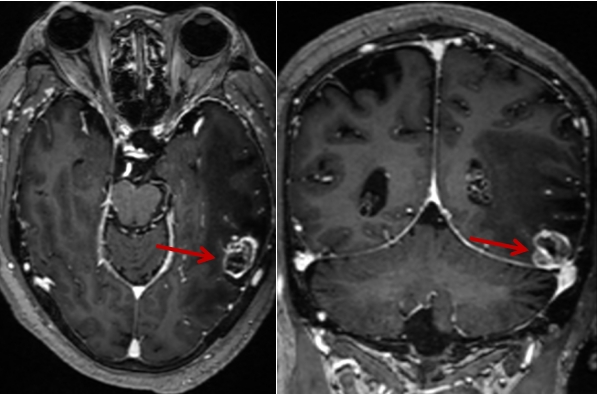

近日,79岁刘爷爷(化名)因“头痛头晕伴恶心呕吐2小时”,被家属紧急送入我院神经外科。入院后经过头部CT及增强MRI检查,其结果提示患者左侧颞叶底部肿瘤,并伴大片脑水肿,病情危重,随时有脑疝形成导致死亡的风险。

图1 术前头部MRI增强扫描(肿瘤组织强化明显,周围脑组织水肿明显)